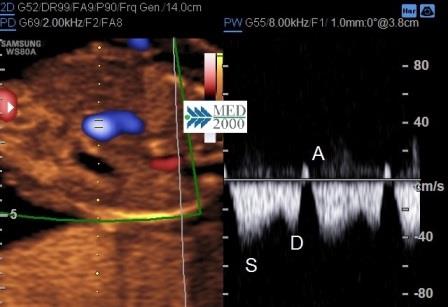

Il razionale dello studio del flusso nel dotto venoso è legato al fatto che nei feti con anomalie cromosomiche e con malformazioni cardiache si può avere una inversione dell'onda relativa alla contrazione atriale (onda A). L'inversione dell'onda A nel dotto venoso si riscontra nel 65% dei feti affetti da Trisomia 21. Normalmente l'onda flussimetrica caratteristica del dotto venoso è rappresentata da:

- onda S caratteristica delle sistole ventricolare

- onda D caratteristica della fase protodiastolica

- onda A caratteristica delle contrazione atriale

Un'onda A invertita si associa ad un rischio elevato per:

- anomalie cromosomiche

- cardiopatie congenite

- morte fetale

Tuttavia in circa l'80% dei casi in cui l'onda A è invertita l'outcome della gravidanza è normale.